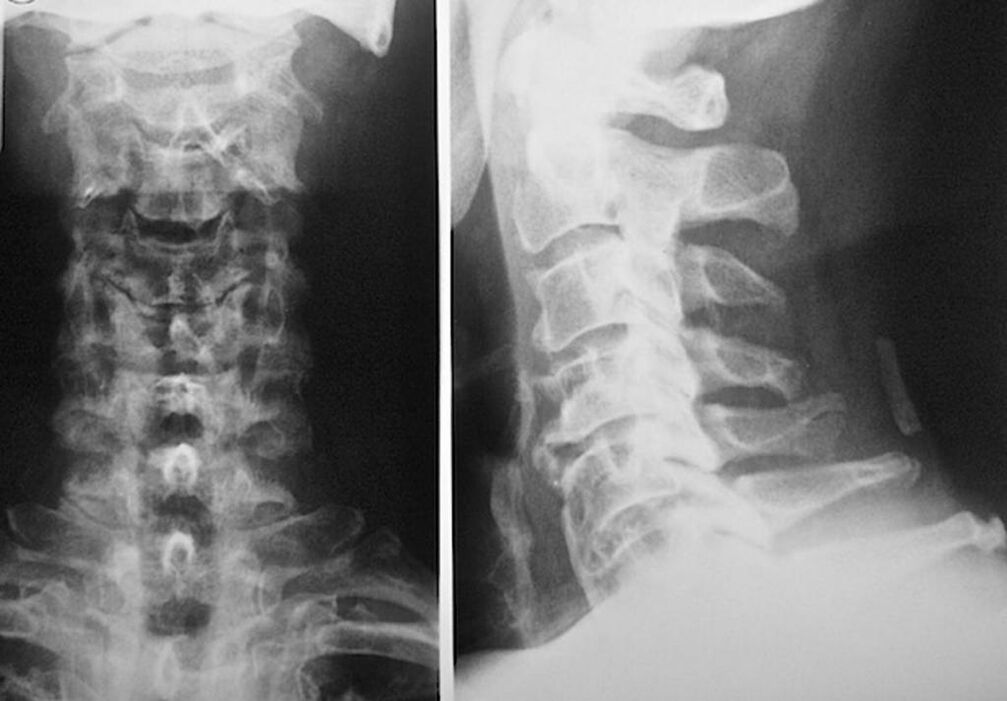

Diagnosis of osteochondrosis: which doctor to consult

To diagnose osteochondrosis of the cervical vertebra and determine the course of treatment, you must register with a neurologist and orthopedist. A neurologist can prescribe tools for the manifestations of the disease, which affects the condition of the nerve endings. If the disease is accompanied by radicular syndrome, it makes sense. The orthopedist will assess the condition of the spine and determine the presence of additional diseases: scoliosis, lordosis, etc.

The following research methods are used to diagnose and accurately assess the condition of the intervertebral discs:

- Radiography.

- CT scan.

- Magnetic tomography.

- Ultrasound examination of cervical veins.

Each of them is completely safe for health and does not pose a risk of overdose. Diagnosis of osteochondrosis of the cervical spine, which will be treated for life, can be made after a simple visual examination. Any orthopedist can do this easily. The exception is the first stage of the disease in which no visible pathology of the cervical region is observed.